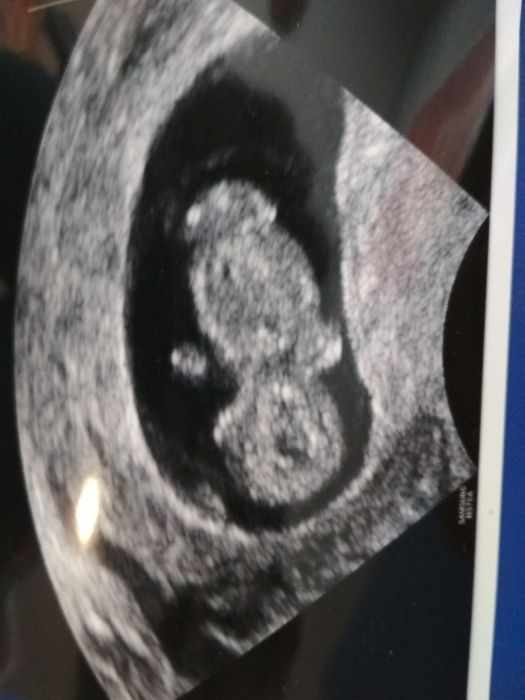

[1064786] tak podle utz jsem dnes cca 9+6tt :) prcek už je pěkný čipera :D

[1066822] juu krasny obrazek. Též jsem chtěla manželovi vzit ale když jsem viděla jen takovy nerozpoznatelny flicek musí si jeste počkat

[1066822] Jůůů - mrňousek!!